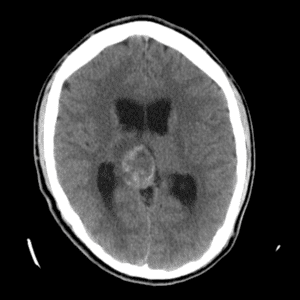

Case #11

Medulloblastoma